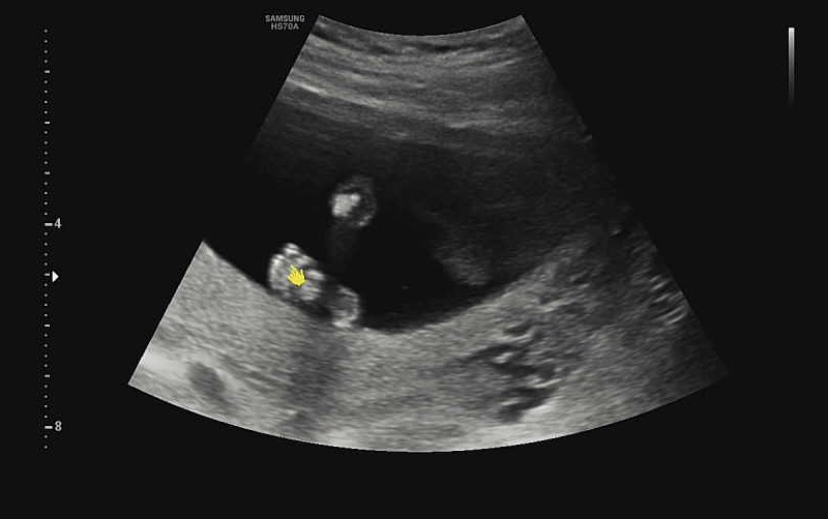

그리고 귀여운 허벅지 공개! 허벅지 뼈가 보였다. 허벅지 뼈 길이도 아이의 성장에 중요한 요소인지 길이를 꼼꼼히 쟀다.